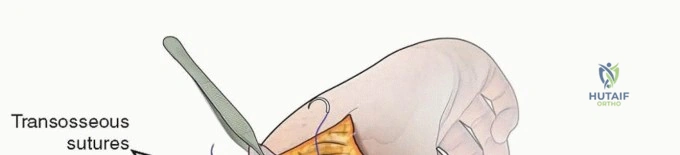

- Articular Reconstruction: The first step is the anatomical reduction of the trochlea and capitellum. The articular fragments are meticulously cleaned of hematoma and interposed periosteum. They are reduced using pointed reduction forceps and provisionally stabilized with smooth K-wires. Definitive fixation of the articular block is achieved using intercondylar compression screws (typically 2.5 mm, 3.0 mm, or 3.5 mm headless compression screws or partially threaded cancellous screws). The screw trajectory must be carefully planned to avoid violating the olecranon or coronoid fossae, which would mechanically block elbow motion.

- Metaphyseal Attachment: Once the articular block is reconstructed, it is reduced to the humeral shaft. In younger children with robust periosteum, crossed K-wires or a combination of K-wires and a single column plate may provide sufficient stability.